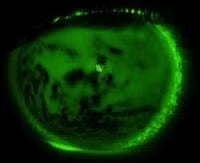

Ocular surface anatomy

Successful fitting of contact lenses, particularly large diameter rigid lens designs, needs a close association between the shape of the contact lens and the shape of the anterior ocular surface. Using eye mould impression techniques, we have developed a database of ocular surface shape which can be manipulated to derive an average ocular surface shape for different refractive errors. This work is in collaboration with Dr Jennifer Turner at Cardiff University.